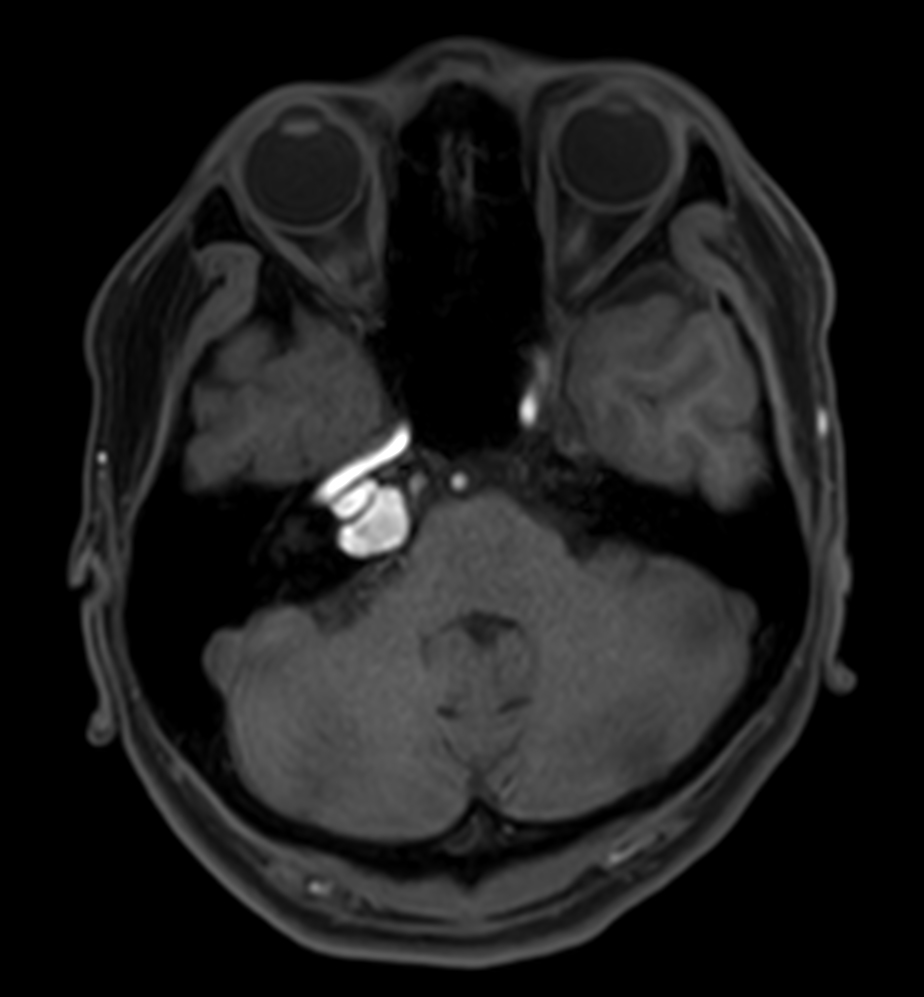

Patient with an IAC lesion. Comparing different DWI methods (EPI, TSE, ZOOM). Compressed SENSE is added to all TSE sequences to decrease scan times, thereby shortening the time the patient has to spent in the magnet. The dS Head 32ch coil is used to enhance image quality.

DWI EPI ZOOM (b1000)